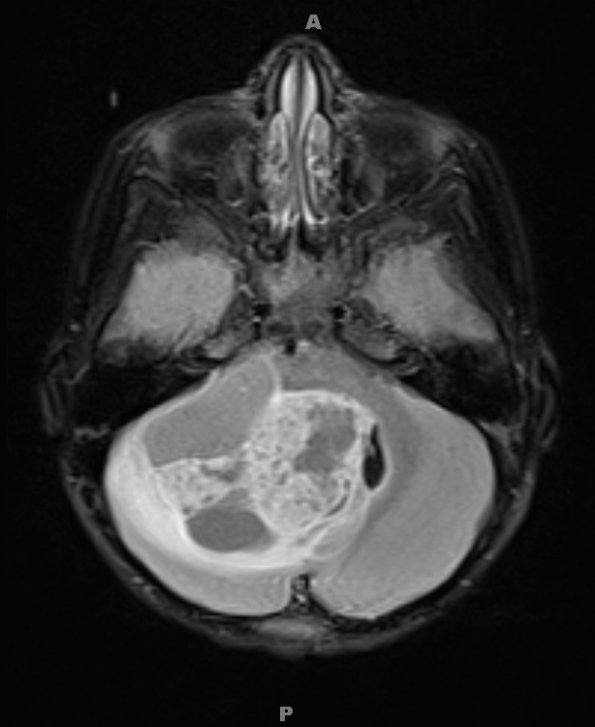

Case 4 ---- 4 year old male, cerebellar mass with BRAF fusion rearrangement. ---- 4A1,2 MRI images of FLAIR imaging (4A1) and T1-weighted contrast administered scan enhancing tumor (4A2).